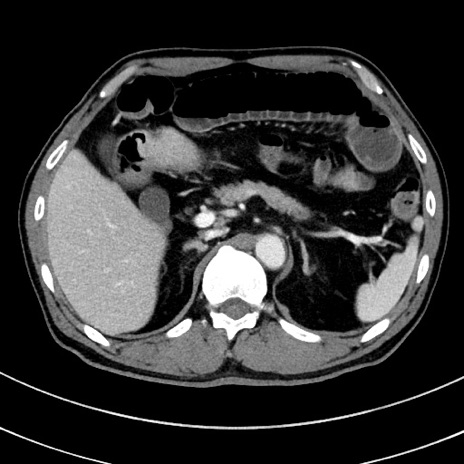

症例8(横断像)

【症例】 60歳代男性

【主訴】 黒色吐物

【現病歴】 4日前から嘔気自覚、2日前の朝食後にも嘔気あり、自分で手で嘔吐反射起こし嘔吐したところ血が混ざっていたため受診。

【既往歴】 5年前汎発性腹膜炎を伴う急性虫垂炎で手術、高血圧、前立腺肥大症、高脂血症

【身体所見】 腹部正中に手術癩痕あり 腹部平坦・軟圧痛なし膨満感あり

【データ】WBC 8400、CRP 4.54